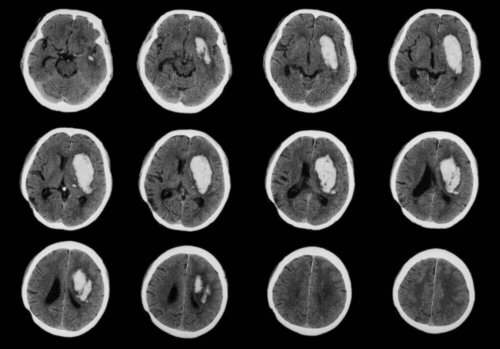

Tumorer opstår som følge af ukontrolleret celledeling i et område af kroppen. Efterhånden dannes der indre knuder, som kan være godartede eller ondartede (kræft). Det er blevet bevist, at denne ændring skyldes en mutation i disse cellers arvemateriale.

En vigtig observation her er, at hjernetumorer aldrig viser sig som knuder på ydersiden af hovedet. Da hjernetumorer ændrer hjernecellerne, udvikler kræften sig inde i dette organ.

Denne sygdom skader aldrig neuronerne, da disse celler i nervesystemet ikke gennemgår celledeling. Derfor vil denne patologi påvirke neuroglia, de celler, der ledsager, nærer og beskytter neuronerne.